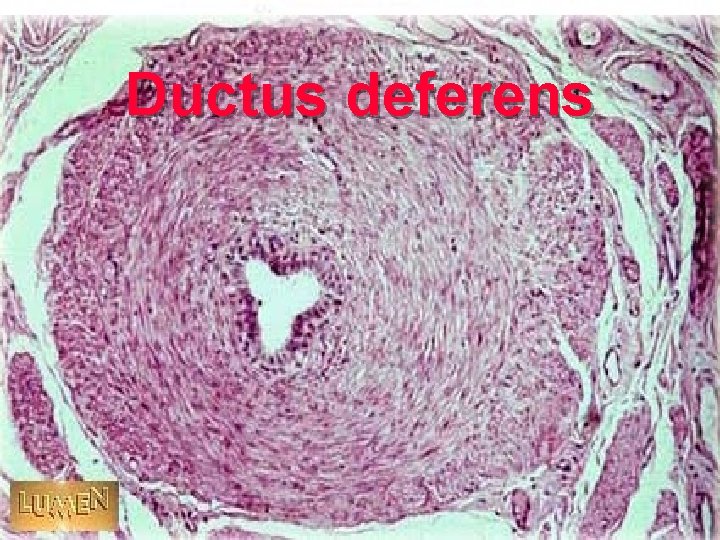

三 ductus deferens lmucosa+muscular wall + adventitia lpseudostratified ciliated columnar Epi. =principal C + basal Cinner lmuscular wall : longitudinal, middle circular, outer longitudinal SMC

Ductus deferens

Ductus deferens